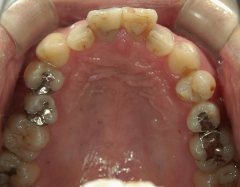

矯正歯科 治療前矯正歯科 治療前

矯正歯科 治療前 上顎の左右4番計2本を抜歯し叢生を改善。

矯正_灰色.pngno.24_8228_治療前_上.jpg矯正_灰色.png